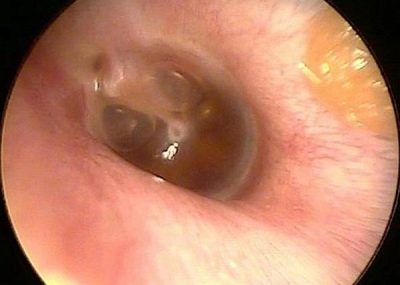

В дополнение к положительному результату теста при надавливании на козелок, выявить наличие воспалительного процесса в ушке у младенца можно только при осмотре уха.

Для более подробного изучения необходимо выполнить инструментальную диагностику состояния слухового прохода и барабанной перепонки. Этот метод называется отоскопией. С его помощью можно обнаружить повреждения барабанной перепонки и выявить наличие гнойных или серозных выделений.

Внешний признак среднего отита, который можно заметить с помощью специального инструмента — отоскопа.